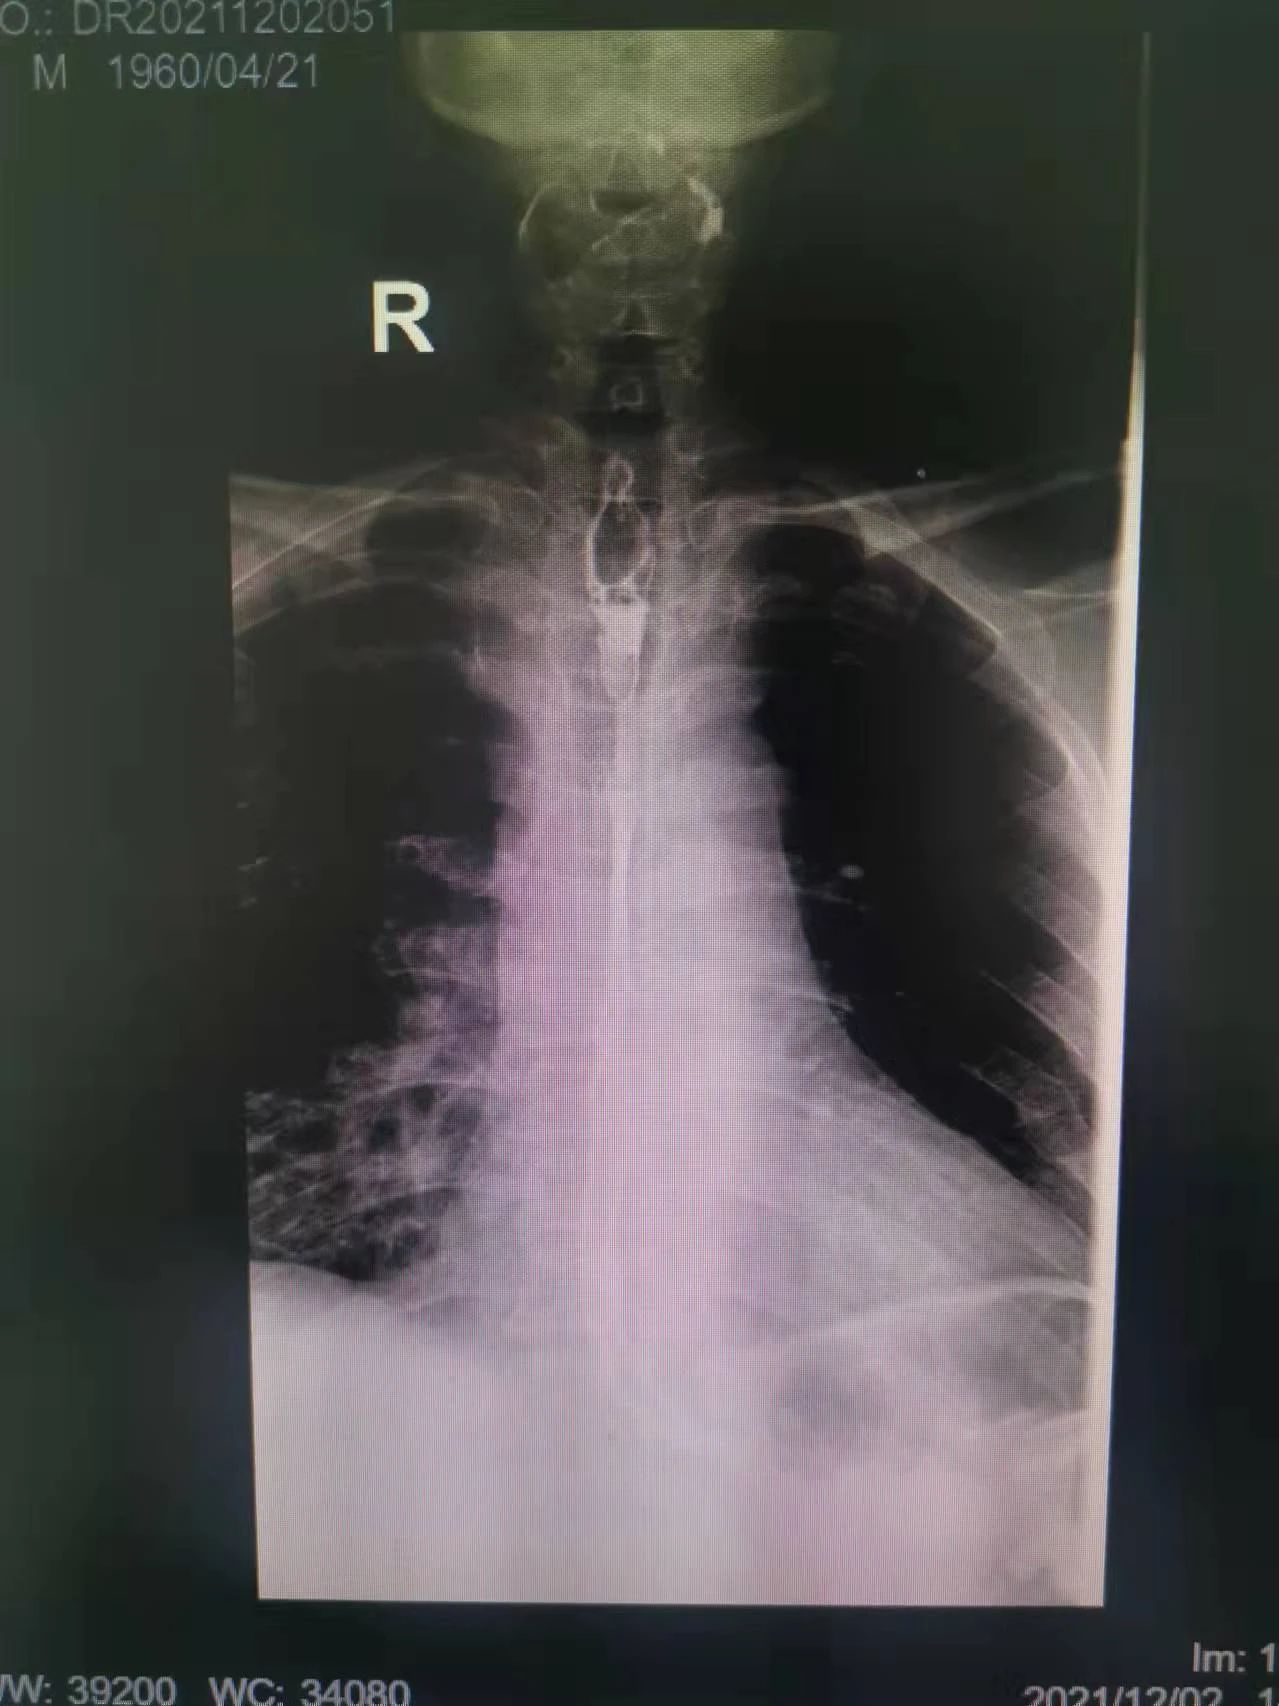

在這種情況下,我院介入二科侯主任決定通過(guò)介入治療中的食管支架植入來(lái)幫助患者實(shí)現(xiàn)這個(gè)愿望。手術(shù)當(dāng)日,侯主任在機(jī)器的幫助下,將一根細(xì)細(xì)的導(dǎo)絲穿過(guò)腫瘤到達(dá)付大爺胃部,然后再沿著導(dǎo)絲,把壓縮好的支架放在腫瘤里面。通過(guò)后撤導(dǎo)管,把壓縮的支架打開,支架把腫瘤撐開,讓食管不再堵塞。有了支架的支撐,付大爺就可以自由地吃東西了,哪怕食管和氣管有溝通,因?yàn)橹Ъ芨采w了腫瘤,通道堵住了,吃的東西也不會(huì)吸到肺內(nèi)造成感染。這時(shí)痛痛快快地吃上一頓,也不再是奢望!

手術(shù)很順利,付大爺也在術(shù)后第2天喝到了自己日思夜想的清水,露出了久違的笑容。從某種意義上講,介入食管支架置入術(shù)的成功實(shí)施,付大爺不能進(jìn)食的病已經(jīng)“治好”了,雖然從生理角度來(lái)說(shuō),付大爺可以通過(guò)終生使用腸內(nèi)營(yíng)養(yǎng)來(lái)維持生存,但我們所做的是致力于給予患者更好的生存體驗(yàn),或者說(shuō)是尊嚴(yán)。銘記并保持一名醫(yī)者的初心,我們要做的正如那句著名的墓志銘所說(shuō):有時(shí)去治愈,常常去幫助,總是去安慰。